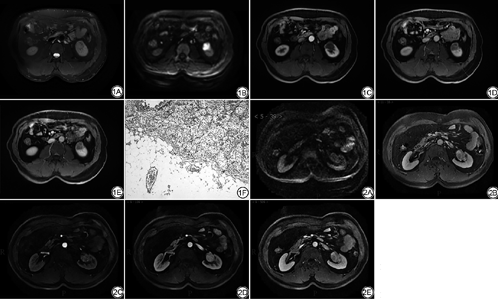

(1) MRI测量肿瘤径线的准确性:在T2WI、DWI、增强扫描实质期T1WI图像上测量的肿块最大径及病理测量的肿块最大径分别为:(5.22±3.28) cm、(5.03±3.08) cm、(5.31±3.37) cm、(5.24±3.59) cm。经Wilcoxon秩和检验四者间差异无统计学意义。T2WI上测量的径线与病理最为接近。(2) MRI评价肿瘤边缘:边界清楚117例(63例肿块可见T2WI环形或半环形低信号假包膜);边缘模糊7例;瘤周脂肪间隙条片或结节灶63例。病理提示肿块未见周围脂肪浸润134例,周围脂肪浸润53例。其中边缘模糊的7例肿块中5例病理均未见脂肪浸润。以肿块边界清楚或边缘模糊作为肿块局限于肾实质内,瘤周脂肪间隙出现条片或结节灶作为肿瘤周围脂肪浸润的诊断标准,MRI评价肿瘤侵犯周围脂肪的敏感度、特异度、阳性预测值、阴性预测值分别为88.7%、88.1%、74.6%和95.2%。(3)增强MRI评价肾静脉瘤栓:以肾静脉管腔增宽,增强扫描实质期腔内可见充盈缺损作为肾静脉瘤栓的诊断标准,其敏感度、特异度、阳性预测值及阴性预测值分别为90.9%、99.2%、98.0%、96.4% (表2;图1,2)。(4)肾细胞癌多参数MRI检查与病理肿瘤T分期一致性检验(Kappa检验):加权Kappa值为0.81,一致性较好。(5) 2名医师间一致性为0.88 (0.84,0.91),具有较好的可重复性。

欧洲指南推荐T1期肾癌首选保留肾脏的肿块切除手术,而T2期肿瘤如果技术允许也可选择保留肾脏手术。但是对于T3及T4期肿瘤推荐全肾切除手术。因此影像提示肿瘤局部浸润(即T3a肿瘤),会影响临床治疗方案的制订,同时提示肿瘤预后较差[17]。T3a的影像诊断征象包括:肾窦脂肪浸润、肾周脂肪及肾静脉瘤栓。Davidiuk等[18]报道CT评价T3a肾细胞癌的敏感度和特异度分别为59%~88%和71%~93%,其中肾窦脂肪浸润的敏感度最高,肾血管瘤栓的特异度最高。MRI因其成像特点,能够更清晰地显示肿块的边缘,假包膜征象的出现更容易将T1、T2期肿瘤与T3a期肿瘤区分开。本研究中肾窦及肾周脂肪浸润的阴性预测值较高,达到95.2%。本组病例中有2例病理T3a期的肿瘤因边缘略模糊被MR评价为1期(图1),同时有11例T1期和1例T2期的肿瘤因可疑病灶周围脂肪浸润而被MR高估为T3a期肿瘤(图2)。这可能是由于肿瘤压迫肾周脂肪,导致肾被膜模糊,使MR难以除外肾被膜受侵。同样的研究也发现横轴位扫描在评价肾被膜是否受累时存在困难。Catalano等[19]采用1 mm的多排CT评价肾被膜受累敏感度、特异度及准确度分别为96%、93%和95%。Roy等[20]报道MRI诊断T3a期肿瘤的敏感度、特异度及准确度分别为84%、95%和91%。因此当出现肾被膜模糊的征象时对T3a的诊断要慎重对待,应根据患者的综合情况进行个体化的治疗。

MRI薄层增强扫描对于血管有很好的显示,以肾静脉管腔增宽,腔内软组织信号充盈缺损伴强化作为静脉瘤栓的诊断标准[21],本组病例中2例因肿块较大并突向肾窦生长使肾静脉分支显示不清,导致MRI漏掉肾静脉分支血栓,造成了肿瘤的低估。另外本组研究中9例肿瘤被MRI高估为T3c。其中3例腔静脉受压明显狭窄,MRI误诊为肿瘤直接侵犯腔静脉,另6例因腔静脉管壁异常信号并强化被MRI误诊为腔静脉管壁受侵。文献报道术前MR成像能够可靠地确定肾细胞癌患者的腔静脉壁的浸润[22]。